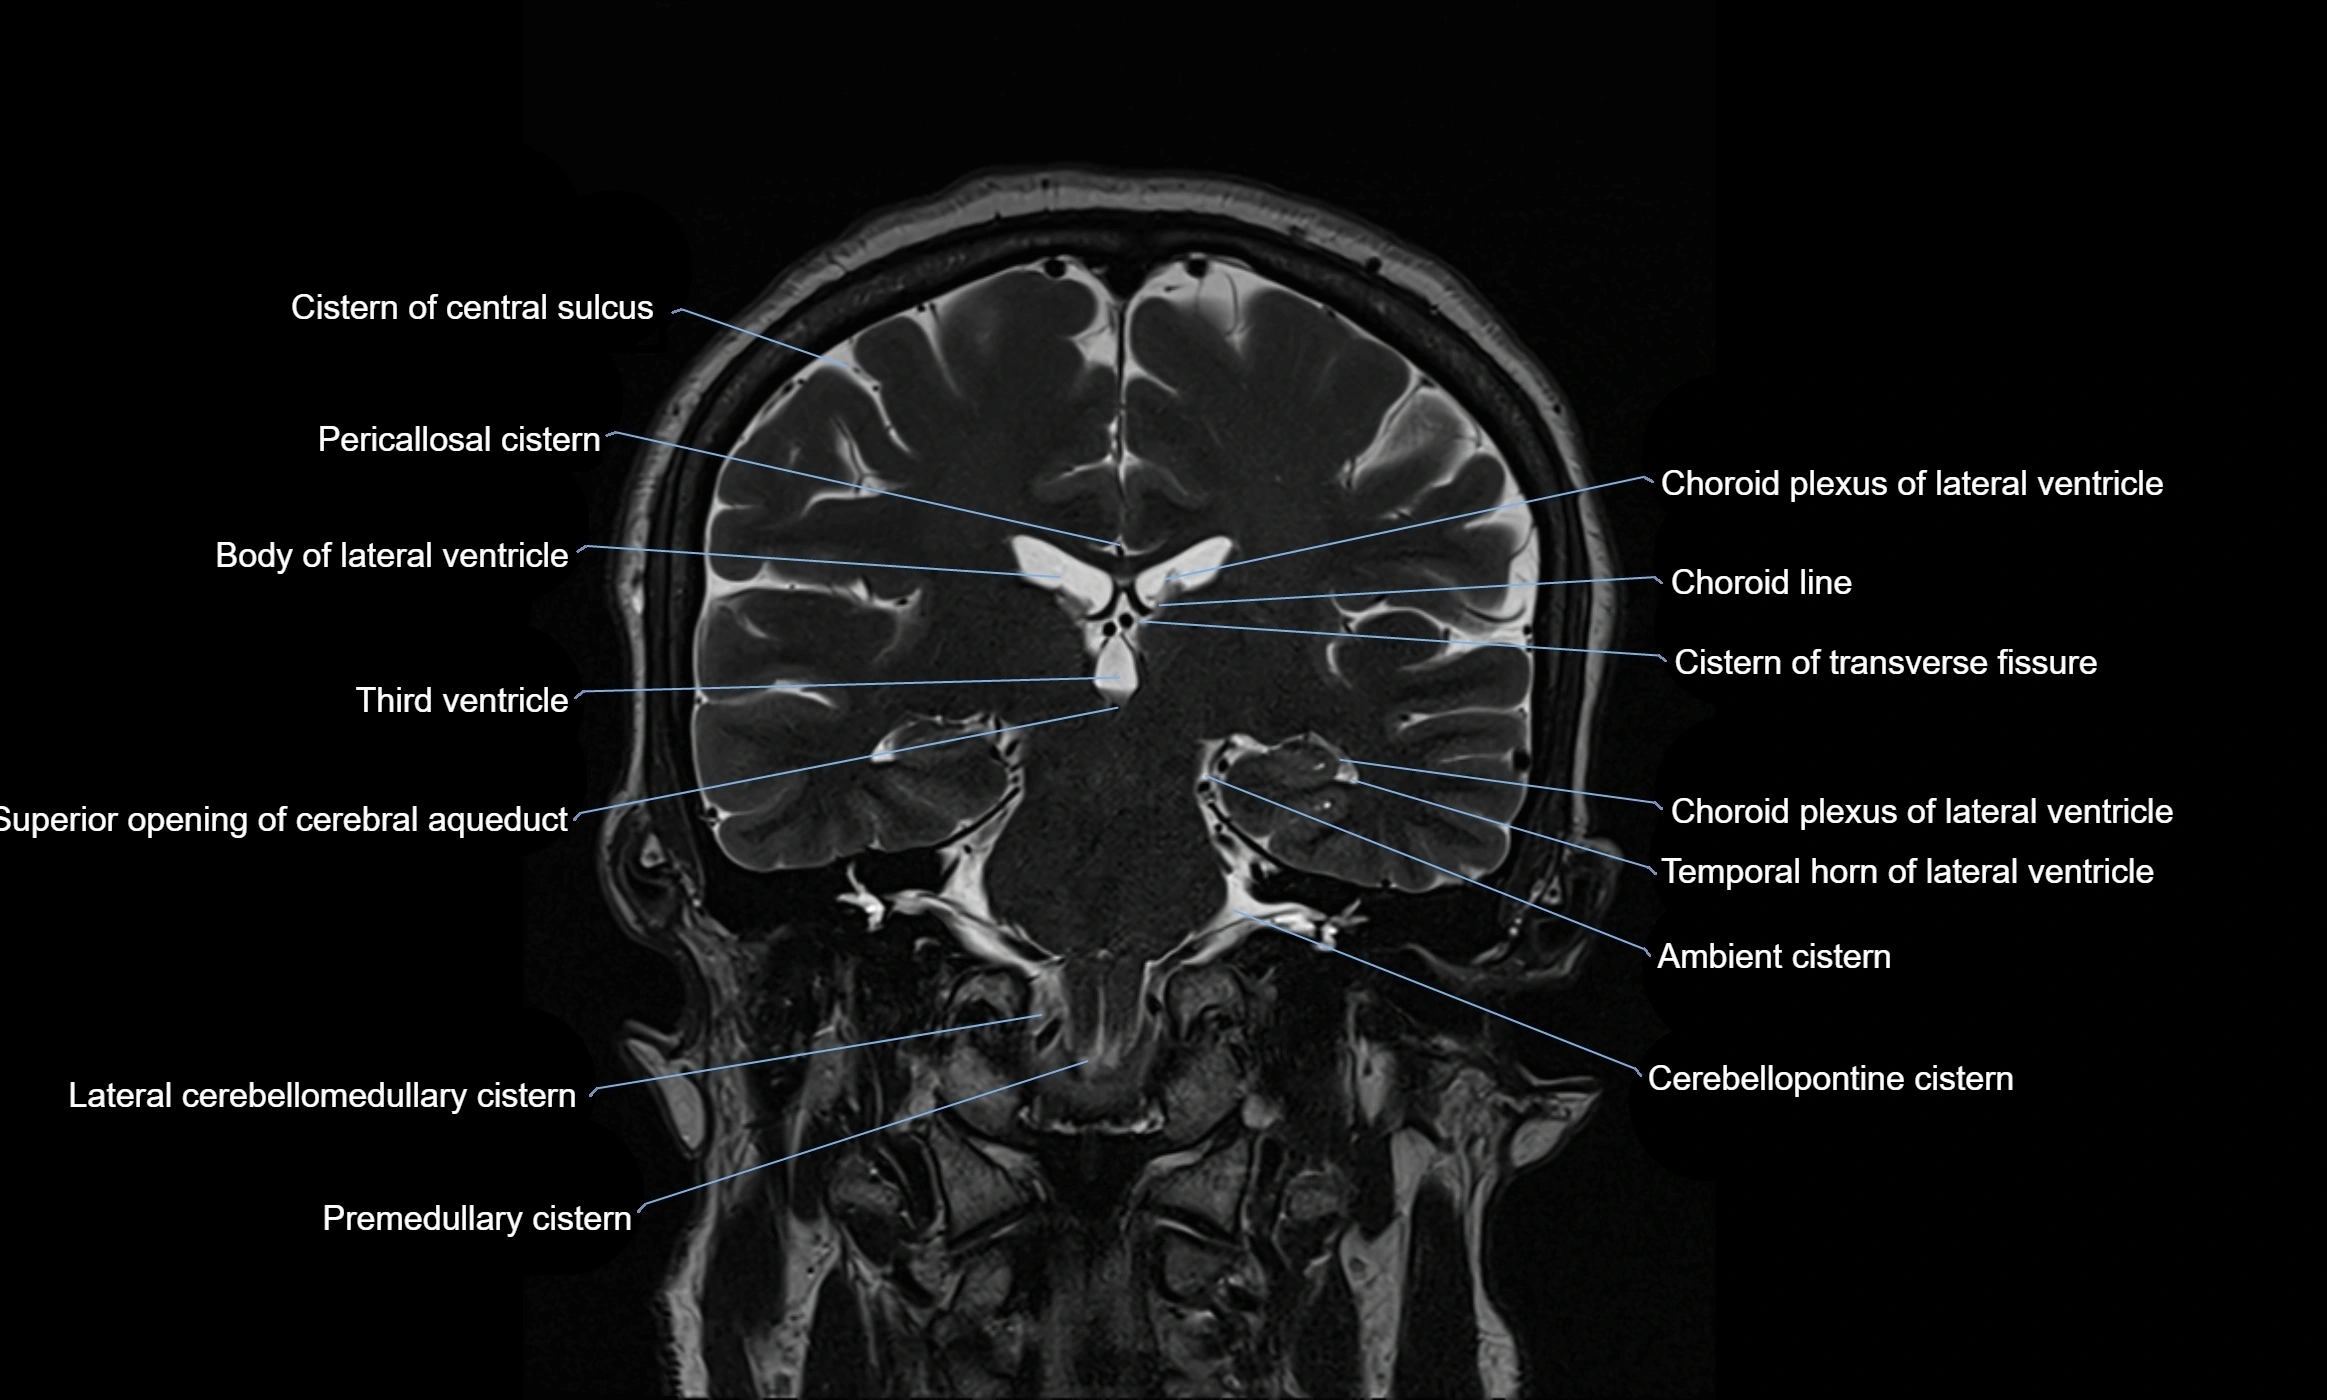

MRI images

image